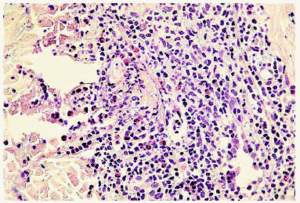

El estudio histopatológico demuestra, en la primera fase o celulítica, un edema en la dermis que está infiltrada por leucocitos, predominantemente eosinófilos, que raramente pueden extenderse a la hipodermis o al músculo. No hay signos de vasculitis. Más tarde, el infiltrado descrito se acompaña de histiocitos y aparecen las características «figuras en llama» compuestas por haces de colágeno degenerado marcadamente eosinófilo rodeadas por un infiltrado granulomatoso (fig. 7). La aparición de las «figuras en llama» se debe al depósito de la proteína básica mayor del eosinófilo en las fibras de colágeno. Aunque se pretendió que estas figuras eran patognomónicas del síndrome de Wells, se han encontrado en otras enfermedades, incluyendo las picaduras de insecto, el penfigoide ampolloso o las parasitosis, entre otras64-67. En la fase de resolución se produce una desaparición gradual de los eosinófilos, con la presencia aún de histiocitos y células gigantes alrededor de las figuras en llama formando microgranulomas62.

Fig. 7.--Celulitis eosinofílica: figuras «en llama».